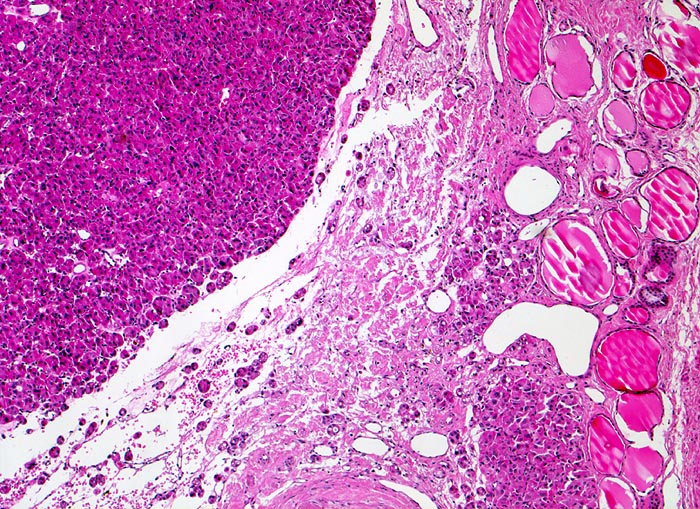

PathoPic – image database / PathoPic ID 4842 - follikuläres Schilddrüsenkarzinom

follikuläres Schilddrüsenkarzinom

Das Karzinom erscheint als solide zellreiche Tumormasse und unterscheidet sich morphologisch deutlich vom angrenzenden makrofollikulären Parenchym. Die breite Tumorkapsel wird von malignen Follikeln durchsetzt. Jenseits der Kapsel ist Tumorgewebe erkennbar, das die Kapsel durchbrochen hat und unmittelbar an das normale Parenchym angrenzt.

Ein follikuläres Schilddrüsenkarzinom kann bewiesen werden, wenn entweder (1) die Kapsel des follikulär gebauten Knotens vom Tumor durchbrochen wird und das Karzinomgewebe das angrenzende Schilddrüsengewebe infiltriert oder (2) Tumoreinbrüche in Gefässe (meistens Kapselvenen) nachweisbar sind oder (3) der Tumor bereits makroskopisch klar invasiv wächst (grob invasives Karzinom)